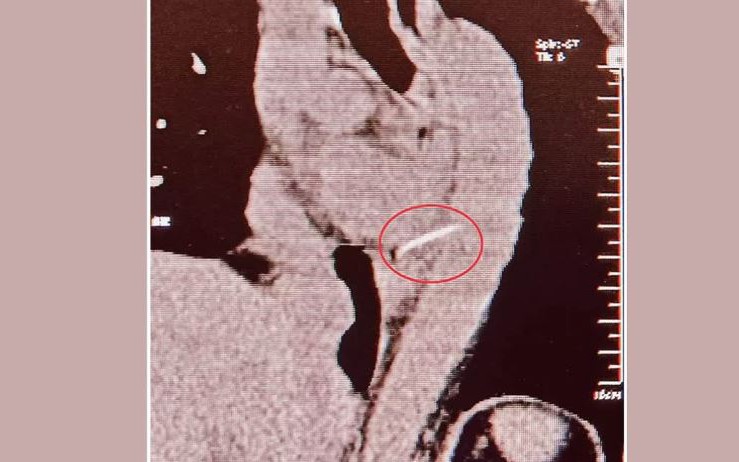

Bệnh viện Thanh Nhàn tiếp nhận bệnh nhân trong tình trạng đau bụng dữ dội do vô tình nuốt phải chiếc tăm tre sắc nhọn hai đầu. Qua thăm khám, các bác sĩ phát hiện dị vật đã cắm sâu gần nửa chu vi thành dạ dày, gây nguy cơ thủng, xuất huyết và biến chứng nguy hiểm.

Trong phòng thủ thuật, ê-kíp nội soi do bác sĩ Nguyễn Thị Hồng Hạnh thực hiện phải làm việc trong bầu không khí căng thẳng. Mọi thao tác đều đòi hỏi sự chính xác tuyệt đối, bởi chỉ cần một sơ suất nhỏ khi rút chiếc tăm cũng có thể gây thêm nhiều vết thủng, dẫn đến chảy máu ồ ạt và nguy hiểm tính mạng.

Sau thời gian tập trung cao độ, chiếc tăm cuối cùng cũng được gắp ra an toàn và nhanh chóng cầm máu và che phủ tổn thương tại vị trí dị vật. Khoảnh khắc ấy, cả ê-kíp vỡ òa, nhẹ nhõm sau những giây phút căng thẳng đến nghẹt thở. Hiện bệnh nhân đã ổn định, không xuất hiện biến chứng và đang tiếp tục được theo dõi tại bệnh viện.